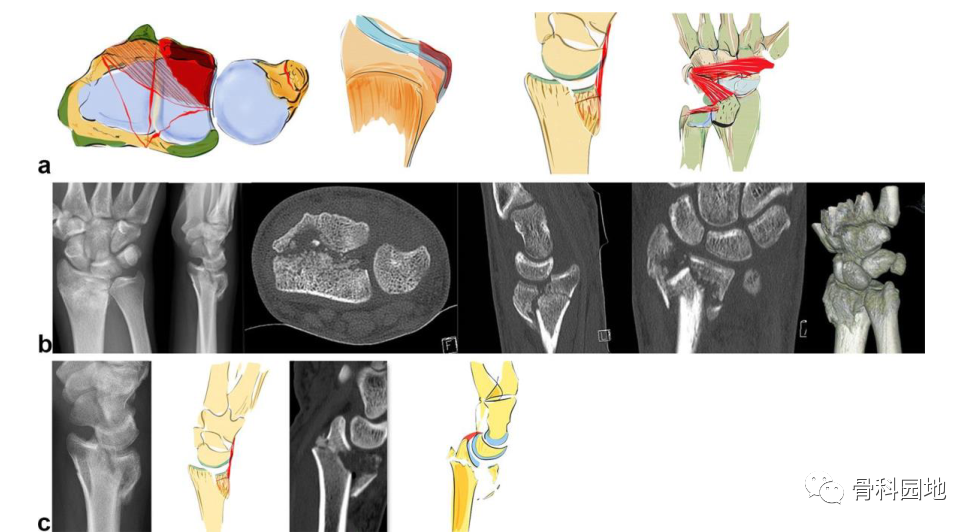

2、掌侧关节骨块

注:可以是大的或较小的边缘碎片。可能发生掌侧脱位,而背侧韧带保持完整 (a)。掌侧骨块:重要的尺桡韧带和尺腕韧带的起源 (b)。向掌侧脱位(c)。掌侧骨折从尺侧延伸到桡侧(d)。在 X 光平片上很容易忽略小的掌侧尺骨骨块,但轴位 CT 扫描容易显示该骨块 (e)